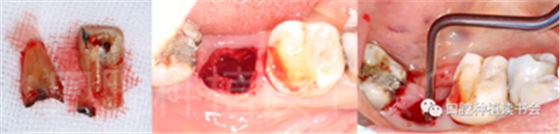

圖1 無法保留的上頜隱裂后牙,拔牙后即刻種植。

后牙區(qū)或者是非美學區(qū)即刻種植,對于患者和臨床醫(yī)生而言,存在一些明顯的優(yōu)勢;比如更小的外科創(chuàng)傷、更短的愈合周期、更少的椅旁時間、更高的患者接受度以及更低的治療費用等。除此之外,在上頜后牙區(qū)即刻種植還可以減少上頜竇的氣化現(xiàn)象【Sharan等.2008】;但并非所有的后牙位點都適合即刻種植,后牙區(qū)即刻種植對醫(yī)生的技術和經(jīng)驗要求更高;由于解剖等諸多條件的差異,美學區(qū)即刻種植的臨床注意事項與后牙區(qū)即刻種植存在諸多不同之處;與本文旨在通過詳細的文獻回顧及臨床案例對后牙區(qū)即刻種植治療提供臨床參考。